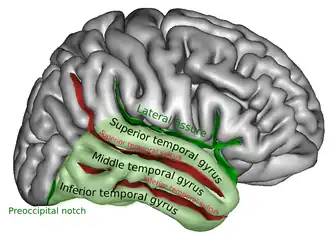

Right temporal lobe (shown in green). Middle temporal gyrus is visible at the middle of the green area. | |